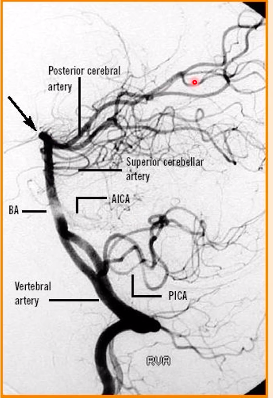

label A-D [4]

A: vertebral artery

B: superior cerebellar artery

C: posterior cerebral artery

D: basilar artery